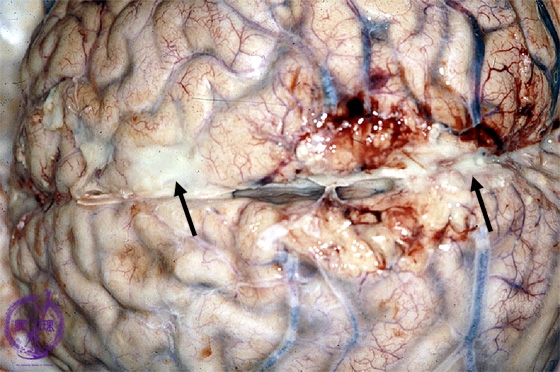

- (3)Purulent meningitis

Macroscopic findings: The arachnoidea was clouded and abscesses were also identified(arrows).